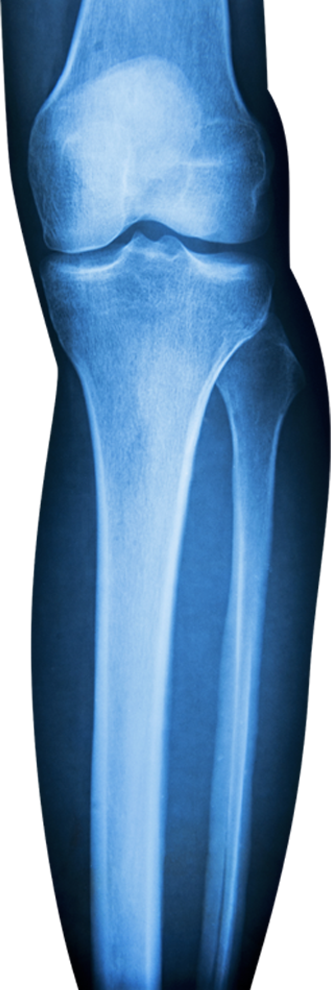

La chirurgie orthopédique et traumatologique est une spécialité traitant les maladies des articulations, des os, des tendons, des ligaments et des nerfs périphériques. Il s’agit d’une chirurgie de la fonction et du mouvement qui privilégie une reprise rapide de l’activité physique du patient et du cours de sa vie.

Cet examen clinique, ainsi que l’analyse des radiographies, IRM, scanner ou autres examens complémentaires, permettent au chirurgien de proposer au patient une prise en charge spécifique : physiothérapie, infiltrations, réalisation d’autres examens complémentaires ou indication d’un traitement chirurgical. Une seconde consultation, voire plus, est nécessaire pour analyser les examens prescrits lors de la première consultation, ainsi qu’une mise au point sur l’évolution de la symptomatologie.